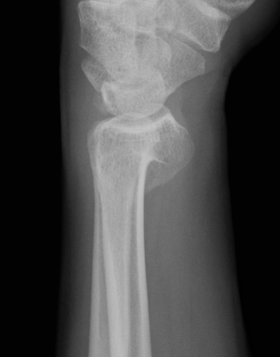

Xray

Bilateral xrays

PA film in neutral

- wrist neutral

- elbow & shoulder at 90°